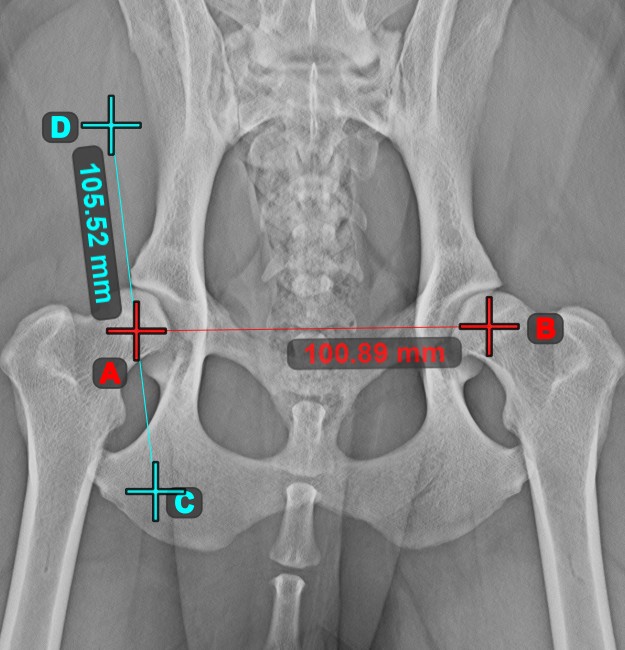

Vonal létrehozása¶

Válassza ki a Vonal létrehozása eszközt, és rendelje hozzá az egyik elérhető egérgombhoz. Helyezze el a kezdő- és végpontot a jelenetben, vagy válassza ki őket a már meglévő pontok közül a képen. A két pont közötti távolság automatikusan kiszámításra kerül az alapértelmezett kalibrációs adatok, vagy a hosszkalibráció mérés által újrakalibrált adatok alapján.

Módosítsa a kezdő- és végpontot az Elem kiválasztása/mozgatása eszközzel. A két pont közötti távolság automatikusan újraszámításra kerül.

Vonal középpontja¶

Azonosítsa és jelölje meg egy új vagy meglévő vonalmérés középpontját a jelenetben a Vonal középpontja eszközzel.

Válassza ki az eszközt a bal oldali eszköztárból, és rendelje hozzá az egyik elérhető egérgombhoz. Helyezze el a kezdő- és végpontot a jelenetben, válassza ki őket a már meglévő pontok közül a képen, vagy válasszon ki egy már meglévő vonalat a jelenetből. A vonal középpontja automatikusan kiszámításra kerül és elhelyezésre kerül a jelenetben. A vonal középpontját mindig a C betű jelzi.